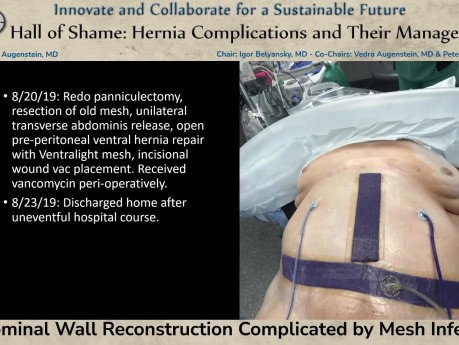

Reconstrucción de la pared abdominal complicada...

La reconstrucción de la pared abdominal complicada por infección de la malla fue presentada en la sesión "Salón de la Vergüenza: Complicaciones de la Hernia y su Manejo" por el Dr. Vedra Augenstein...